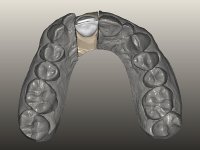

The endocrown should be constructed with a zirconia framework with an ‘intra-root’ and crown components, being this last one veneered with ceramics.

CAD-CAM technology was used to design and construct an endocrown with a zirconia framework veneered with ceramics. The crown was then bonded to the tooth, by using an MDP based adhesive and a dual polymerization composite resin.